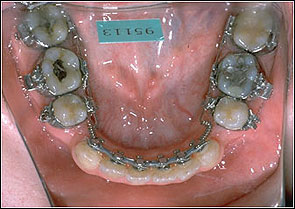

STEP 4. En-mass retraction

Stainless Steel 017*025 (TMA with Closing Loop)